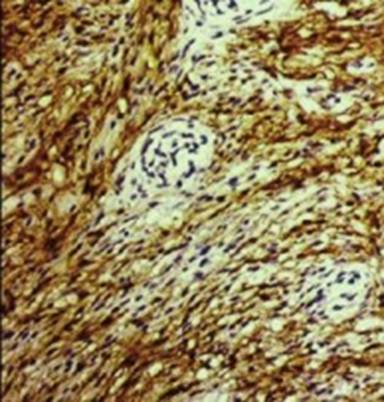

Hematoxylin-eosin stained sections of the specimen showed a highly cellular waving spindle cell proliferation embedded within abundant collagenous and focal myxoid stroma (Figure 3). The spindle cells were running in parallel bundles. Spindle cells were also seen surrounding the acinar cells of the pancreas and proliferating them. The tumor cells showed mild to moderate nuclear pleomorphism with mitotic activity of less than 1 per 10 HPF. No evidence of hemorrhage or necrosis was noted. The tumor was encapsulated and the centre of the tumor also showed pancreatic acinar cells. Immunohistochemical studies showed membranous positivity for epithelial membrane antigen (Figure 4). Stains for CD34 and S-100 protein were negative. In view of the morphology and immunohistochemistry, the diagnosis of perineurioma was made.

Figure 4. Positivity of spindle cells for epithelial membrane antigen |